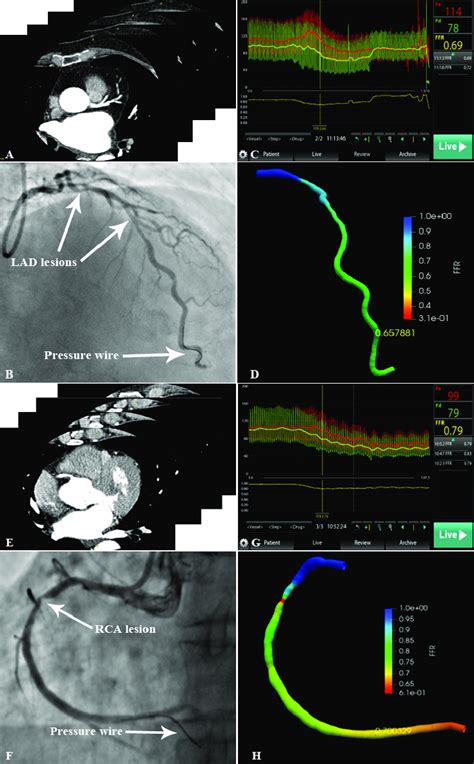

So, you’re probably wondering, “How on earth do they measure this FFR thing?” Great question! The process of measuring Fractional Flow Reserve (FFR) , especially in the Left Anterior Descending (LAD) artery , is a pretty sophisticated procedure, usually done during a cardiac catheterization (also known as an angiogram). It’s not something done out of the blue; it’s typically performed when an angiogram shows a significant-looking blockage in a coronary artery, and the cardiology team needs to determine its functional significance. Here’s the lowdown on how it’s done, guys. First off, the patient is prepped for a standard cardiac catheterization. A thin, flexible tube called a catheter is inserted into an artery, usually in the wrist or groin, and guided up to the heart. Once the cardiologist can visualize the coronary arteries using X-ray and contrast dye, they’ll assess the blockage in the LAD. Now, for the FFR part: a special pressure wire is advanced through the catheter and carefully threaded past the stenosis (the narrowing) in the LAD. This wire has tiny sensors on its tip that can measure pressure. To get an accurate FFR reading, the heart needs to be under maximal blood flow conditions . This is usually achieved by administering a medication, either intravenously or directly into the coronary artery, that causes the blood vessels to dilate (widen) significantly. This medication, often adenosine or a similar vasodilator, simulates the conditions of intense physical exertion or stress. Once maximal hyperemia (high blood flow) is achieved, the pressure sensor on the wire measures the pressure distal to the blockage (further down the artery). Simultaneously, another pressure sensor, either on the catheter itself or a sensor wire left in the aorta, measures the pressure in the aorta. The FFR value is then calculated as the ratio of the distal coronary pressure to the aortic pressure. An FFR value of 1.0 would mean no pressure drop, indicating no significant functional blockage. An FFR value below 0.80 (meaning the pressure beyond the blockage is less than 80% of the pressure before it) generally indicates a physiologically significant stenosis that is likely limiting blood flow to the heart muscle and may warrant treatment. The whole procedure is performed by highly skilled interventional cardiologists, and it provides invaluable objective data to guide treatment decisions, helping to avoid unnecessary interventions and ensure timely treatment for those who will benefit most. It’s a testament to how far cardiac imaging and physiology have come!

Alright, so the FFR measurement has been taken for that Left Anterior Descending (LAD) artery . Now comes the critical part: interpreting those numbers. This is where the magic happens, guys, and where objective data truly guides patient care. The Fractional Flow Reserve (FFR) value is a simple ratio, but its implications are profound. Remember, it’s calculated by comparing the pressure after the blockage in the LAD to the pressure before it (or in the aorta) when the heart is pumping at maximum capacity (hyperemic state). So, what do these numbers tell us?

• FFR ≤ 0.80 : This is the threshold that typically signals a physiologically significant stenosis. An FFR of 0.80 or lower (like 0.75, 0.70, or even less) indicates that the blockage is causing a substantial reduction in blood flow to the heart muscle. When the heart needs more oxygen – during exercise, stress, or even just at rest if the blockage is severe – this reduced flow can lead to symptoms like chest pain (angina), shortness of breath, or even a heart attack. When FFR is in this range, especially in the critical LAD artery, it strongly suggests that the patient would benefit from revascularization – procedures like angioplasty with stenting or coronary artery bypass surgery to restore adequate blood flow.